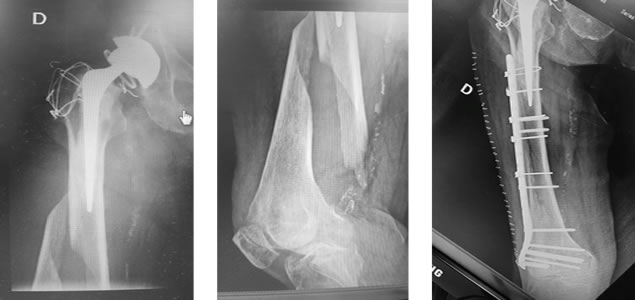

Las fracturas del fémur o del acetábulo pueden ocurrir durante o después de la artroplastía total de cadera. Las fracturas del femur son las más frecuentes, y suelen requerir alguna forma de tratamiento. El tratamiento de la fractura periprotésica depende de varios factores como la ubicación de la fractura, las caracteristicas de la misma, la relación de la fractura con el componente protésico, edad del paciente, espectativa de vida, etc.

El tratamiento es específico para cada caso.